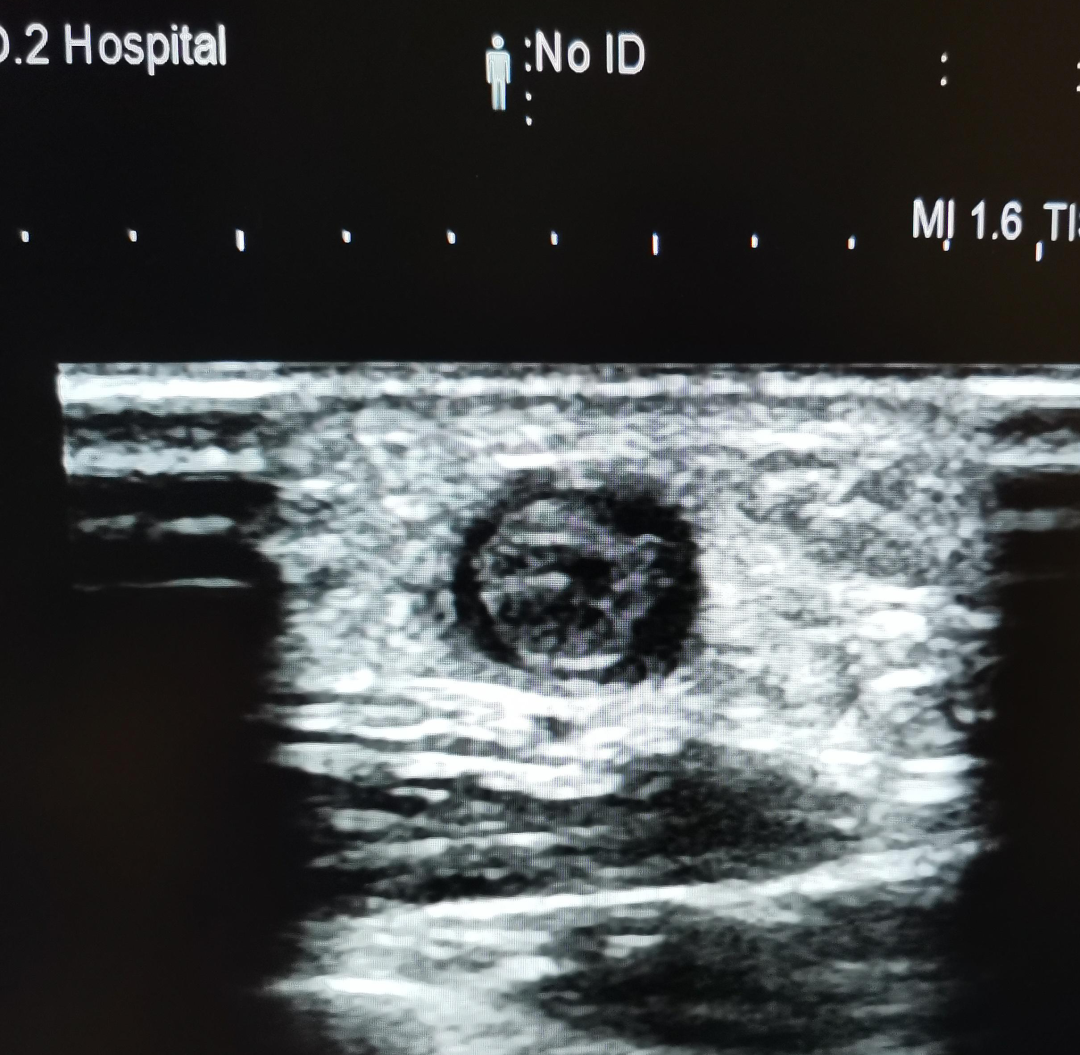

患者術(shù)前

天亮后患者用了將近四個小時的車程趕到!陳醫(yī)師經(jīng)仔細(xì)的體查后,判斷內(nèi)瘺血栓形成并堵塞,立即辦理住院。彩超證實(shí)長段血栓閉塞伴嚴(yán)重內(nèi)膜增生硬化,是我科迄今為止擬行PTA手術(shù)解決的最嚴(yán)重的病變。